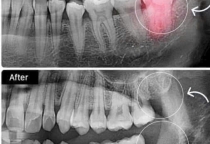

3. Niềng răng mắc cài có cần nhổ răng không?

Nếu răng chen chúc quá mức hoặc hàm hẹp, bác sĩ có thể chỉ định nhổ 1–2 răng tiền cối để tạo khoảng trống.

Trường hợp nhẹ, có thể dùng minivis chỉnh nha thay cho nhổ răng.